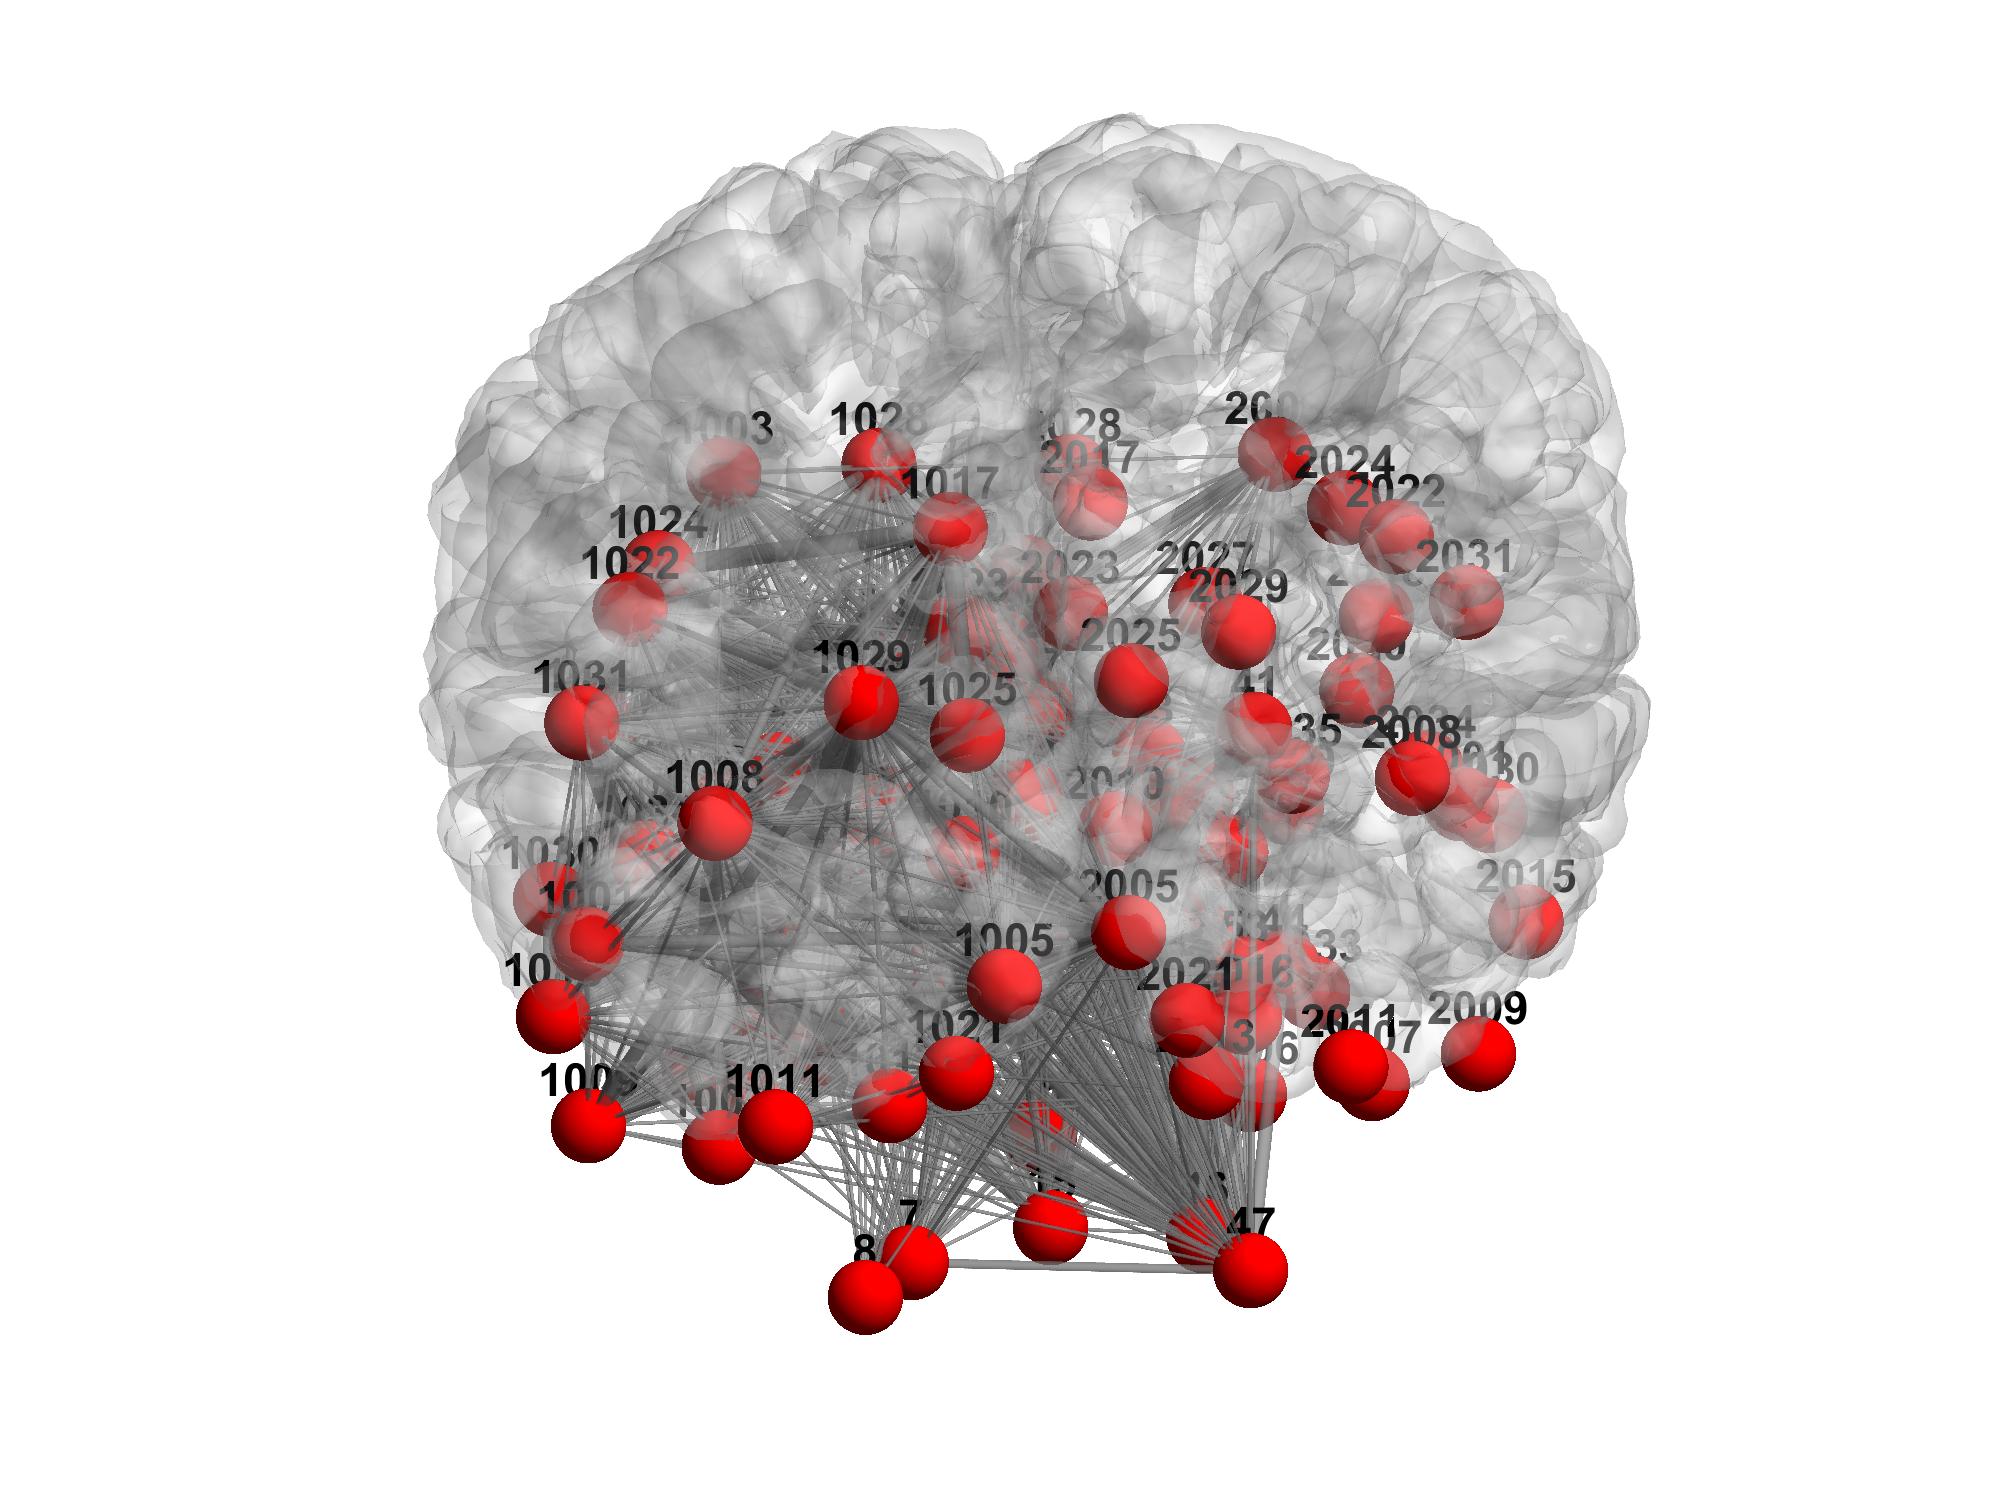

I simply wanted to make sure what I do (both for individual subjects and for consensus) is correct. The resulting connectome I obtain for one example subject is attached in the figures, and I can observe that:

1) nodes do not seem to be perfectly overlaid on the surface (maybe that is just because cerebellum is included in the parcellation, thus causing some nodes to appear outside the pial surface)

2) connections between nodes are "strangely" distributed (i.e., not symmetrical).

In the figures, I selected all nodes and edges with no exclusion/thresholding criteria.